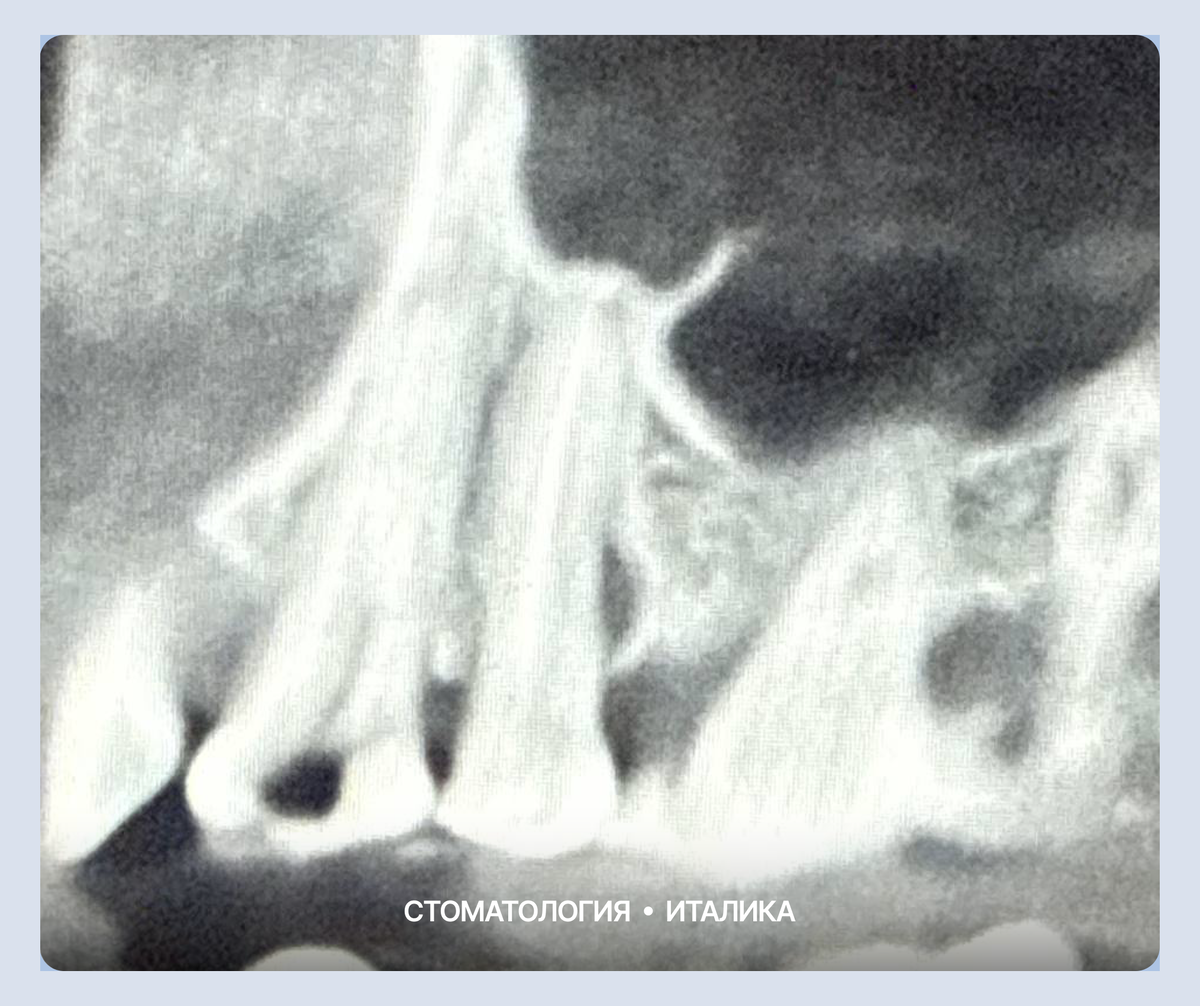

На первом снимке четко видна деструкция костной ткани у корня зуба.

• Внешне это могло никак не проявляться: ни отека, ни острой боли.

• Внутри же шел хронический воспалительный процесс.

• Воспаление буквально «съедало» кость вокруг корня, образуя пустоту (полость). Если бы мы оставили всё как есть, зуб в скором времени стал бы подвижным и отправился на удаление.